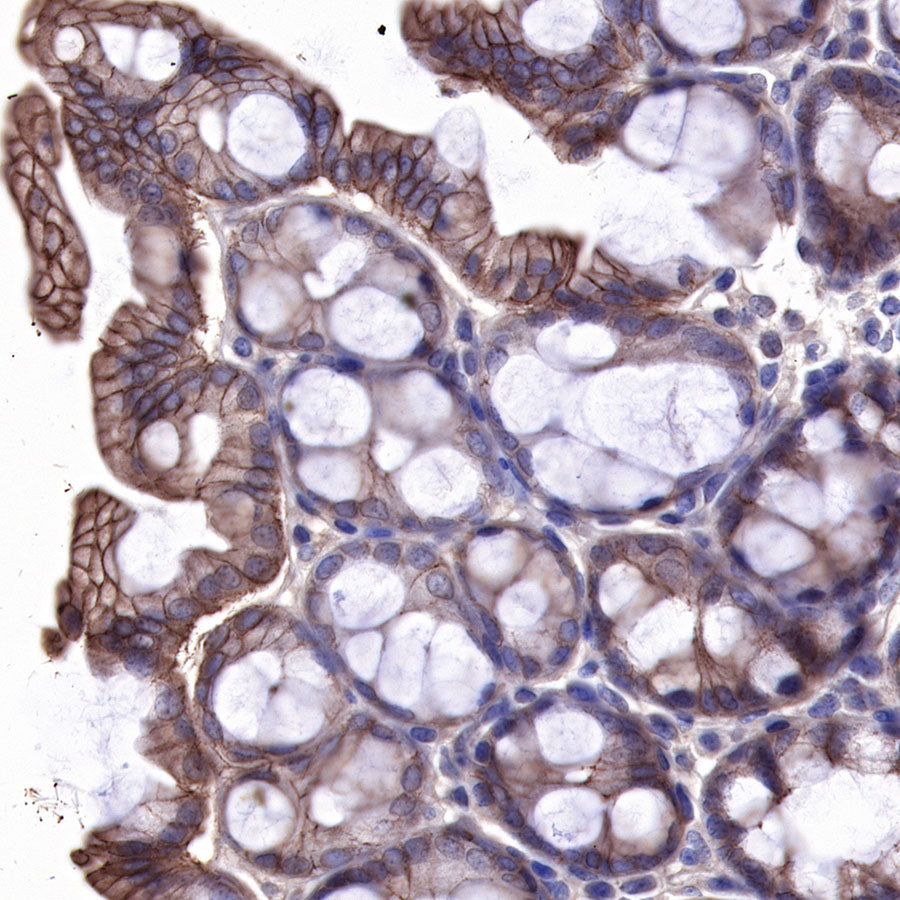

IHC shows positive staining in paraffin-embedded human esophagus. Anti-EGFR antibody was used at 1/2000 dilution, followed by a HRP Polymer for Mouse & Rabbit IgG (ready to use). Counterstained with hematoxylin. Heat mediated antigen retrieval with Tris/EDTA buffer pH9.0 was performed before commencing with IHC staining protocol.

IHC shows positive staining in paraffin-embedded rat stomach. Anti-EGFR antibody was used at 1/500 dilution, followed by a HRP Polymer for Mouse & Rabbit IgG (ready to use). Counterstained with hematoxylin. Heat mediated antigen retrieval with Tris/EDTA buffer pH9.0 was performed before commencing with IHC staining protocol.